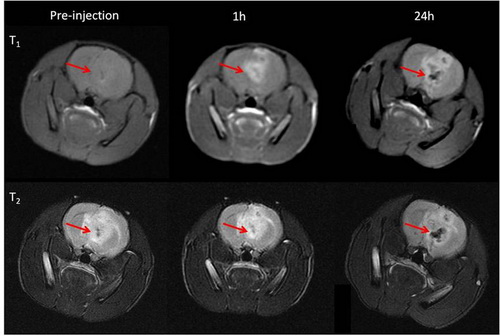

MOF结构钴氰酸锰纳米立方块在小鼠脑部肿瘤部位的磁共振成像应用